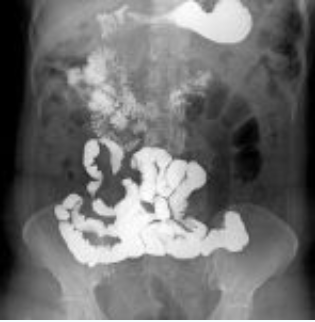

Figura 2: Segmentos do intestino delgado visíveis em trânsito intestinal. Fonte: Radiopaedia

O intestino delgado é dividido em três segmentos:

- Duodeno: localizado retroperitonealmente, em forma de "C", envolve a cabeça do pâncreas.

- Jejuno: ocupa o quadrante superior esquerdo; apresenta pregas circulares (válvulas coniventes) espessas, numerosas e permanentes.

- Íleo: localizado no quadrante inferior direito; pregas mais finas, lúmen mais calibroso e presença de nódulos linfoides agregados (placas de Peyer).

O ponto final do exame é a passagem do contraste pela valva íleo-cecal para o ceco.